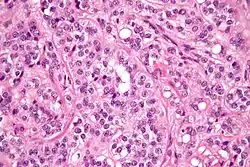

| Micrograph of a granulosa cell tumour, a type of sex-cord–gonadal stromal tumour. H&E stain. | |